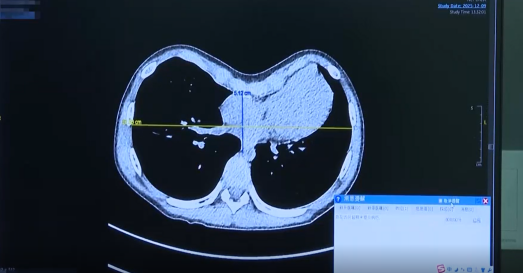

Patient: A young adult with long-standing, severe pectus excavatum.

Challenge: The patient had lived with a deep chest depression for years, which caused self-consciousness and occasional shortness of breath during exertion.

Priority: In addition to effective correction, the patient strongly desired a minimally invasive approach with the smallest possible scars.

Solution & Outcome: Through small, strategically placed incisions on the sides of the chest, our team performed a precise correction using the latest techniques. The profound depression was fully elevated, and thanks to the minimally invasive approach, recovery was swift, with only very small, discreet scars remaining. The patient gained not only a normal chest contour but also the confidence to wear what they wished.